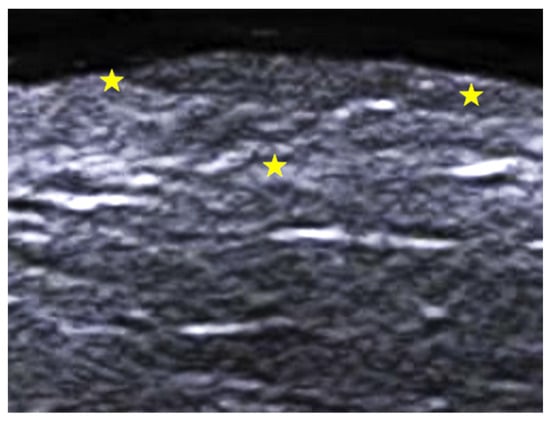

- Parra-Cares, J.; Wortsman, X.; Alfaro-Sepúlveda, D.; Mellado-Francisco, G.; Ramírez-Cornejo, C.; Vera-Kellet, C. Color Doppler Ultrasound Assessment of Subclinical Activity with Scoring of Morphea. J. Cutan. Med. Surg. 2023, 27, 454–460. [Google Scholar] [CrossRef] [PubMed]

- Wortsman, X.; Vera-Kellet, C. Ultrasound Morphea Activity Scoring (US-MAS): Modified US-MAS. J. Ultrasound Med. 2023, 42, 2447–2450. [Google Scholar] [CrossRef] [PubMed]

- Vera-Kellet, C.; Meza-Romero, R.; Moll-Manzur, C.; Ramírez-Cornejo, C.; Wortsman, X. Low effectiveness of methotrexate in the management of localised scleroderma (morphea) based on an ultrasound activity score. Eur. J. Dermatol. 2021, 31, 813–821. [Google Scholar] [CrossRef]